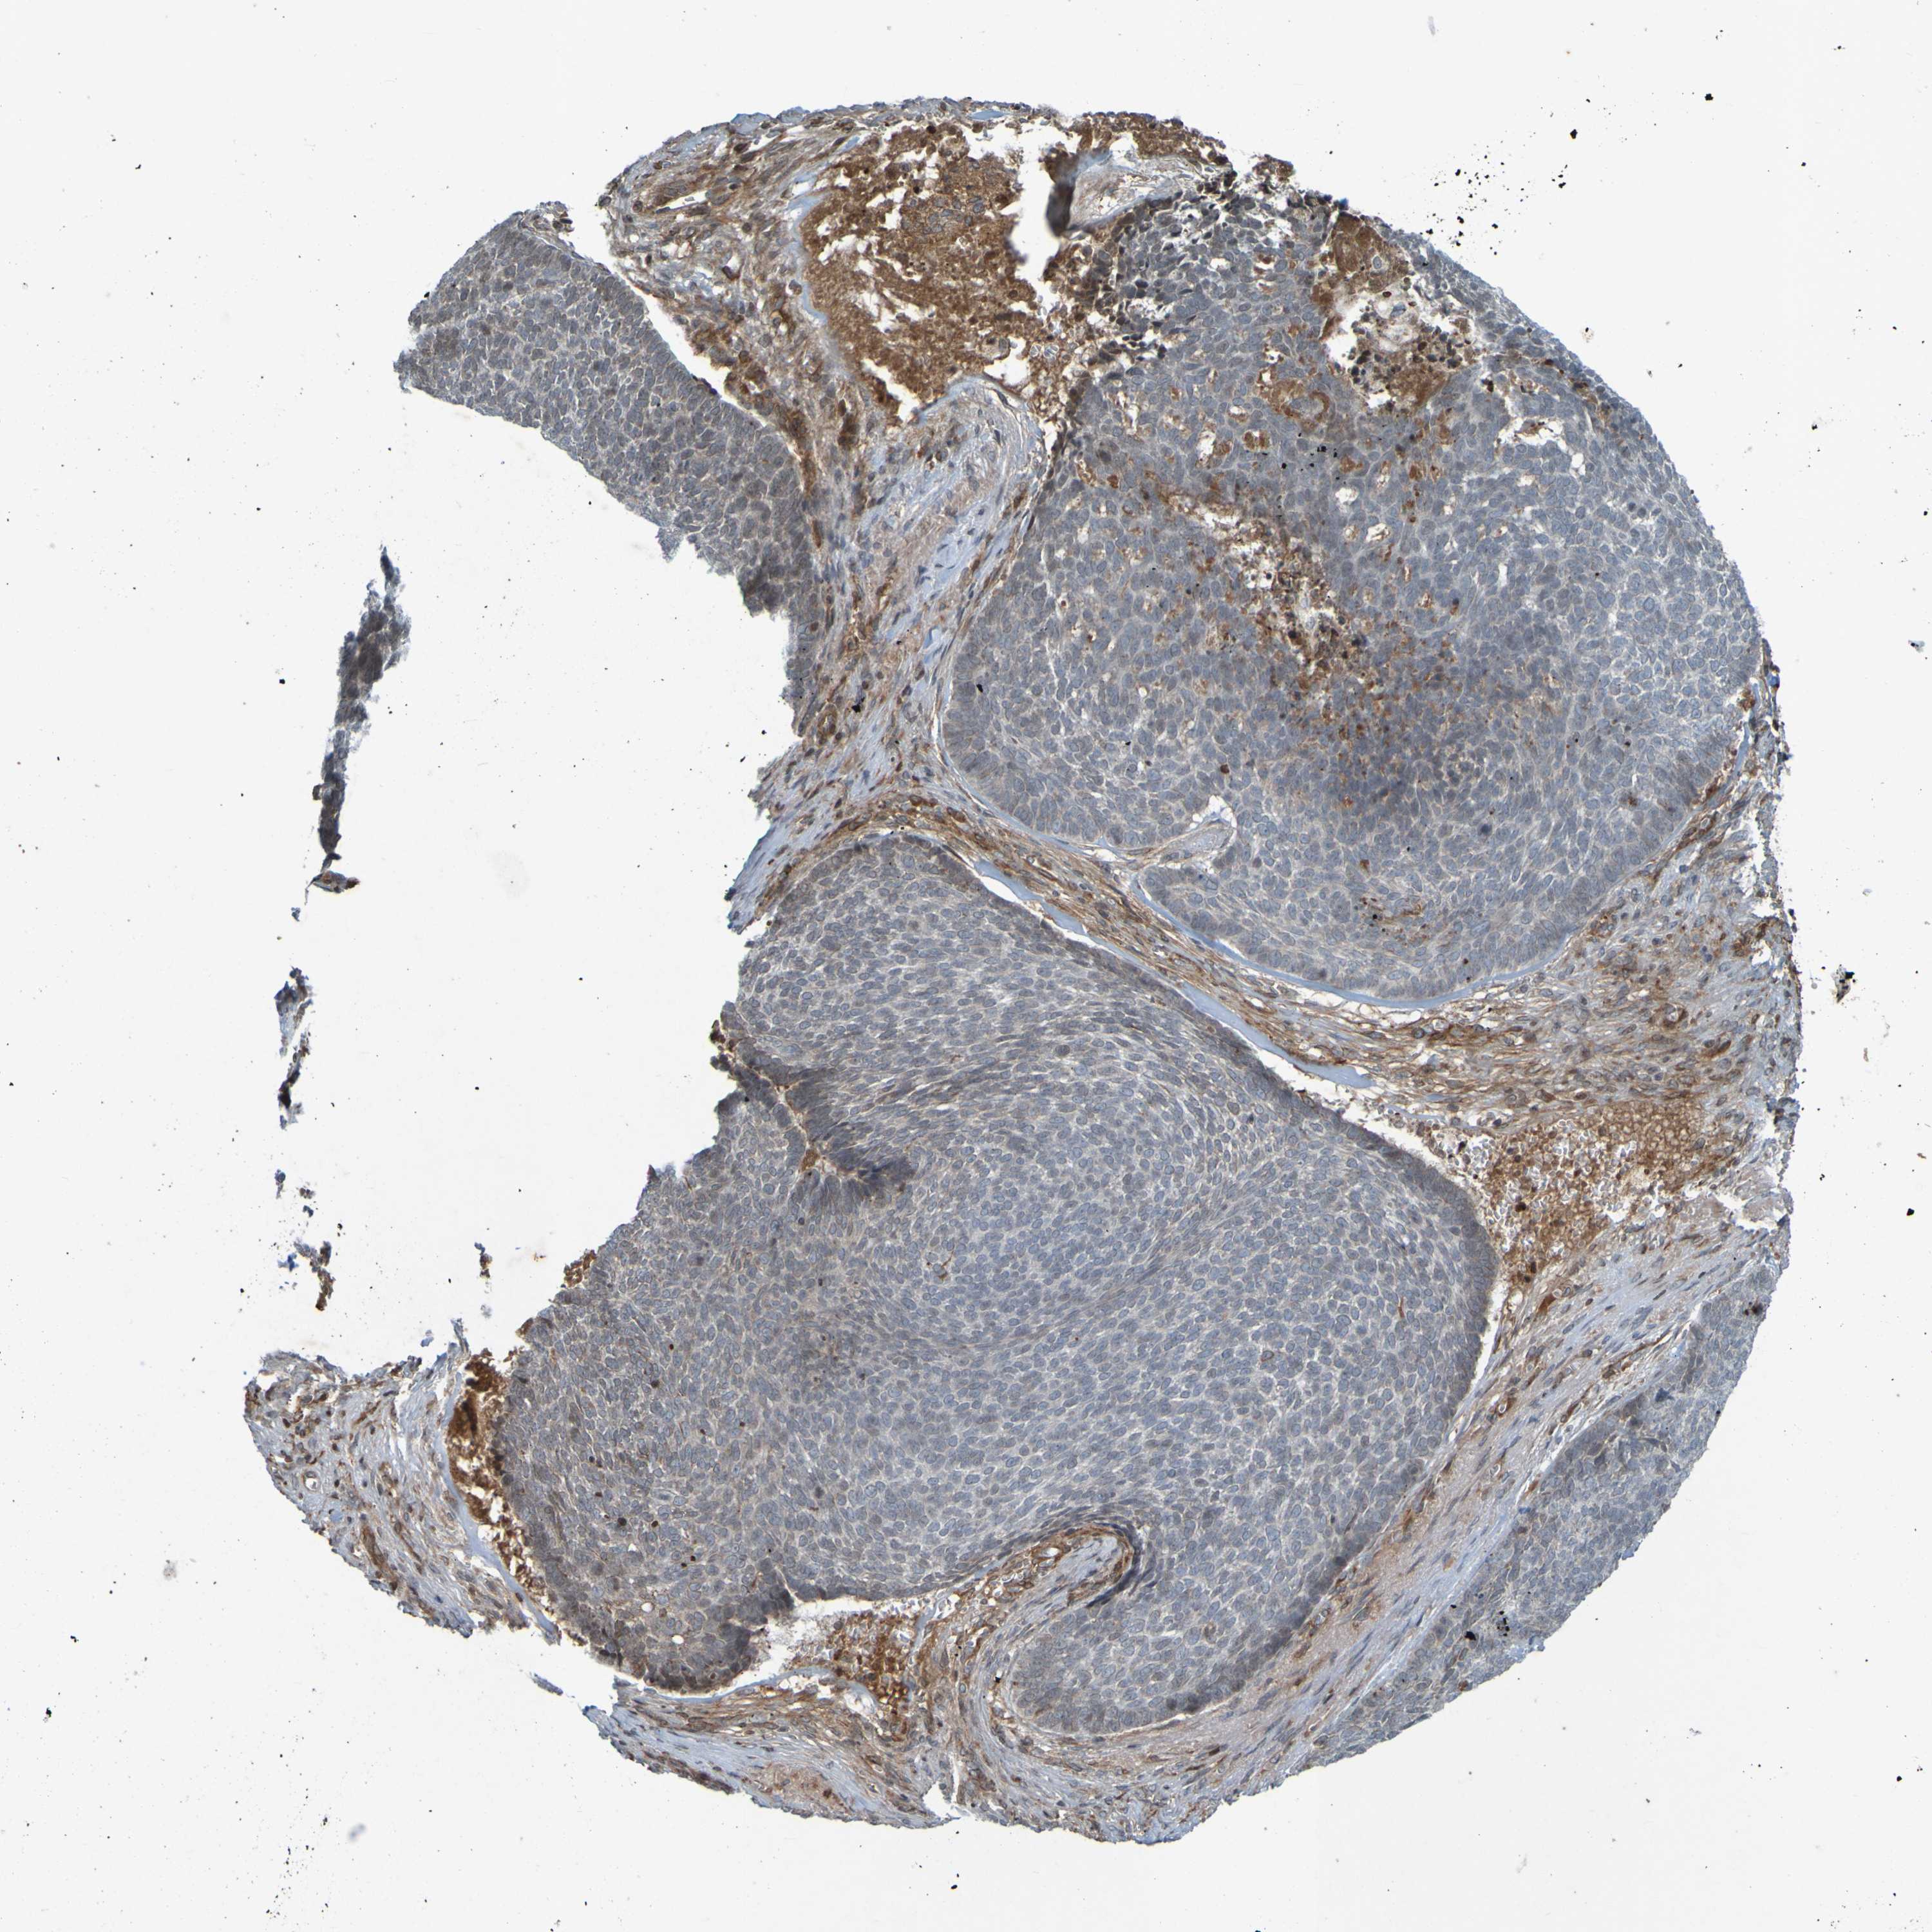

Basal cell and squamous cell cancer

SKIN CANCER - Protein expressioni

A mouse-over function shows sample information and annotation data. Click on an image to view it in a full screen mode. Samples can be filtered based on level of antibody staining by selecting one or several of the following categories: high, medium, low and not detected. The assay and annotation is described here.

Antibody stainingi

Antibody staining in the annotated cell types in the current human tissue is reported as not detected, low, medium, or high, based on conventional immunohistochemistry profiling in selected tissues. This score is based on the combination of the staining intensity and fraction of stained cells.

Each image is clickable and will lead to virtual microscopy that enables deeper exploration of all samples and also displays staining intensity scores, fraction scores and subcellular localization as well as patient and tissue information for each sample.

Antibody HPA056004

Staining

High

Intensity

Quantity

Location

Basal cell carcinoma